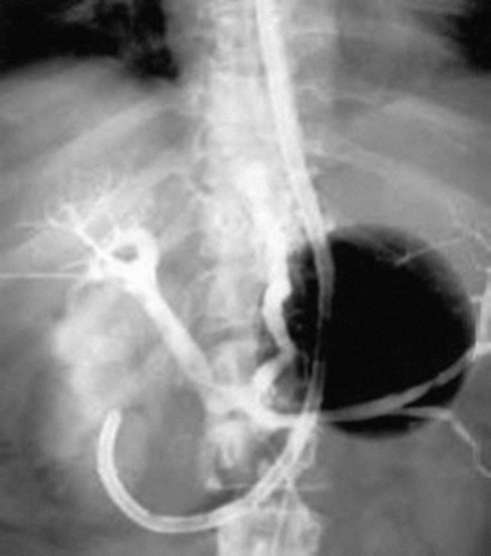

Чрескожная дилатационная трахеостомия (в большинстве случаев в ОРИТ) предпочтительнее открытой трахеостомии, она представляет собой одну из модификаций методики Сельдингера.

• Чрескожную дилатационную трахеостомию можно выполнить у постели с помощью готовых стерильных наборов (рис. 2.60). Это позволяет исключить небезопасную для пациентов ОРИТ транспортировку в операционную.

Методика чрескожной дилатационной трахеостомии (по Григгсу). Чрескожный доступ к дыхательным путям выполняют на уровне подперстневидного пространства (между перстневидным хрящом и первым кольцом трахеи или на уровне от второго до четвертого кольца трахеи). Все методики предусматривают кожный разрез, но он не должен превышать размер устанавливаемой трубки.

• Идентифицируют анатомические ориентиры шеи. Определив область трахеальных колец, врач производит в выбранном месте пункцию иглой со шприцем, заполненным водой. Иглу продвигают вперед, осуществляя аспирацию. Появление пузырьков воздуха свидетельствует о том, что игла в трахее (рис. 2.61, а). Пункцию и положение иглы следует контролировать с помощью бронхоскопа.

• Шприц и иглу удаляют, с помощью аспирации проверяют, что канюля осталась в трахее. Через канюлю вводят проводник, и канюлю удаляют (рис. 2.61, б). Небольшой претрахеальный расширитель вводят по проводнику в трахею, затем удаляют (рис. 2.61, в).

• Специальный дилатационный зажим надевают на проводник, продвигают в трахею (рис. 2.61, г). Нельзя закрывать зажим на проводнике. Вводят кончики зажима в трахею, располагают кольца зажима краниально и разводят их. Раскрытие дилатационного зажима расширяет переднюю трахеальную стенку до размера трахеостомической трубки. Вытаскивают зажим в раскрытом состоянии (рис. 2.61, д).

• Трубку нанизывают на проводник и продвигают в трахею. После этого проводник и обтуратор удаляют, оставляя трахеостомическую трубку на месте. Раздувают манжету трубки для герметизации (рис. 2.61, е). Трахеостомическую трубку фиксируют, удаляют эндотрахеальную трубку.

pic 0071

Рис. 2.61. Методика чрескожной дилатационной трахеостомии по Григгсу: а-е - пояснения в тексте [16]